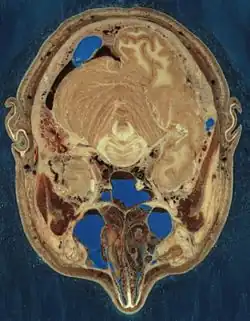

The Visible Human Project is an effort to create a detailed data set of cross-sectional photographs of the human body, in order to facilitate anatomy visualization applications. It is used as a tool for the progression of medical findings, in which these findings link anatomy to its audiences.[1] A male and a female cadaver were cut into thin slices, which were then photographed and digitized. The project is run by the U.S. National Library of Medicine (NLM) under the direction of Michael J. Ackerman. Planning began in 1986;[2] the data set of the male was completed in November 1994 and that of the female in November 1995. The project can be viewed today at the NLM in Bethesda, Maryland.[3] There are currently efforts to repeat this project with higher resolution images but only with parts of the body instead of a cadaver.

The male cadaver was encased and frozen in a gelatin and water mixture in order to stabilize the specimen for cutting. The specimen was then "cut" in the axial plane at 1-millimeter intervals. Each of the resulting 1,871 "slices" was photographed in both film and digital, yielding 15 gigabytes of data. In 2000, the photos were rescanned at a higher resolution, yielding more than 65 gigabytes. The female cadaver was cut into slices at 0.33-millimeter intervals, resulting in some 40 gigabytes of data.

The term "cut" is a bit of a misnomer, yet it is used to describe the process of grinding away the top surface of a specimen at regular intervals. The term "slice", also a misnomer, refers to the revealed surface of the specimen to be photographed; the process of grinding the surface away is entirely destructive to the specimen and leaves no usable or preservable "slice" of the cadaver.

The data are supplemented by axial sections of the whole body obtained by computed tomography, axial sections of the head and neck obtained by magnetic resonance imaging (MRI), and coronal sections of the rest of the body also obtained by MRI.